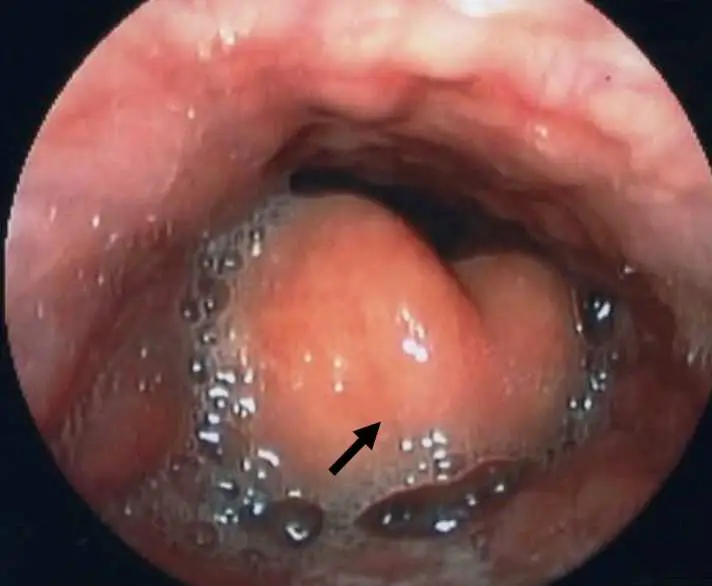

40 歲男性,因發燒、咽喉疼痛、吞嚥困難、呼吸急促等症狀至急診就診,會診耳鼻喉科進行咽喉內視鏡檢查如下圖,下列敘述何者正確?

本內視鏡影像為咽喉直接或間接軟式喉鏡檢查所見。影像中央可見一顆明顯腫脹、呈球狀隆起的鮮紅色(cherry-red)結構,即高度水腫的會厭(epiglottis),黑色箭頭即指向此腫脹的會厭。正常會厭為扁平的葉片狀,而本影像中的會厭已腫大變圓,幾乎占滿聲門入口,周圍可見大量黏稠分泌物及氣泡堆積(提示分泌物無法正常排除)。會厭周圍的杓會厭皺褶(aryepiglottic folds)亦明顯充血水腫。此「鮮紅色腫脹會厭(cherry-red swollen epiglottis)」是急性會厭炎的病理辨識徵象。氣道因此嚴重狹窄,有急性完全氣道阻塞的立即風險。

(A) 箭頭所指為甲狀軟骨(thyroid cartilage)發炎腫脹 ❌ 錯誤。箭頭所指並非甲狀軟骨。甲狀軟骨位於喉的外側,屬於硬性軟骨結構,內視鏡下無法直接如此觀察。影像中箭頭明確指向會厭(epiglottis)——聲門上方呈球形隆起、鮮紅水腫的軟組織結構,為急性會厭炎的典型表現。